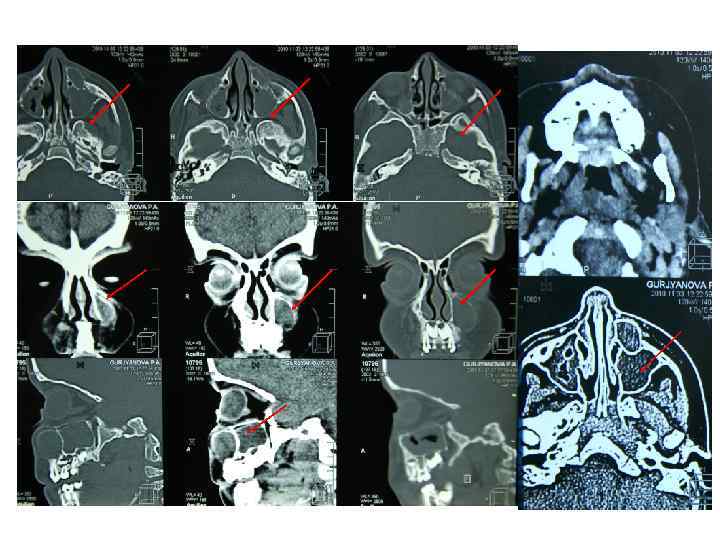

• Компьютерная томография Рентгеновские лучи после прохождения через тело больного воспринимаются детекторами и преобразуются в электрические сигналы, которые поступают в компьютер, где и преобразуются в изображение органов и тканей.

Компьютерная томография имеет следующие преимущества перед обычной рентгенографией: • 1. Возможность получения изображения всех видов тканей (костной, хрящевой, мышечной, жировой и т. д. ); • 2. Позволяет увидеть изображение не только исследуемого органа, но и других органов и тканей, находящихся на данном уровне ("срезе"), определить их форму, величину, топограф-анатомические взаимоотношения; • 3. Можно сложить изображение поперечных срезов и получить продольное изображение органов; • 4. Даёт возможность увеличения в несколько раз патологического очага и проведения точных измерений исследуемой области; • 5. Даёт чёткое изображение тканей при различии их плотности в 15— 20%, тогда как обычная рентгенография — при разнице плотностей, не превышающей 0, 5%; • 6. Позволяет судить об эффективности лечения; • 7. Помогает получить изображение опухоли, размеры которой не превышают несколько миллиметров (не исключены ложноположительные результаты).